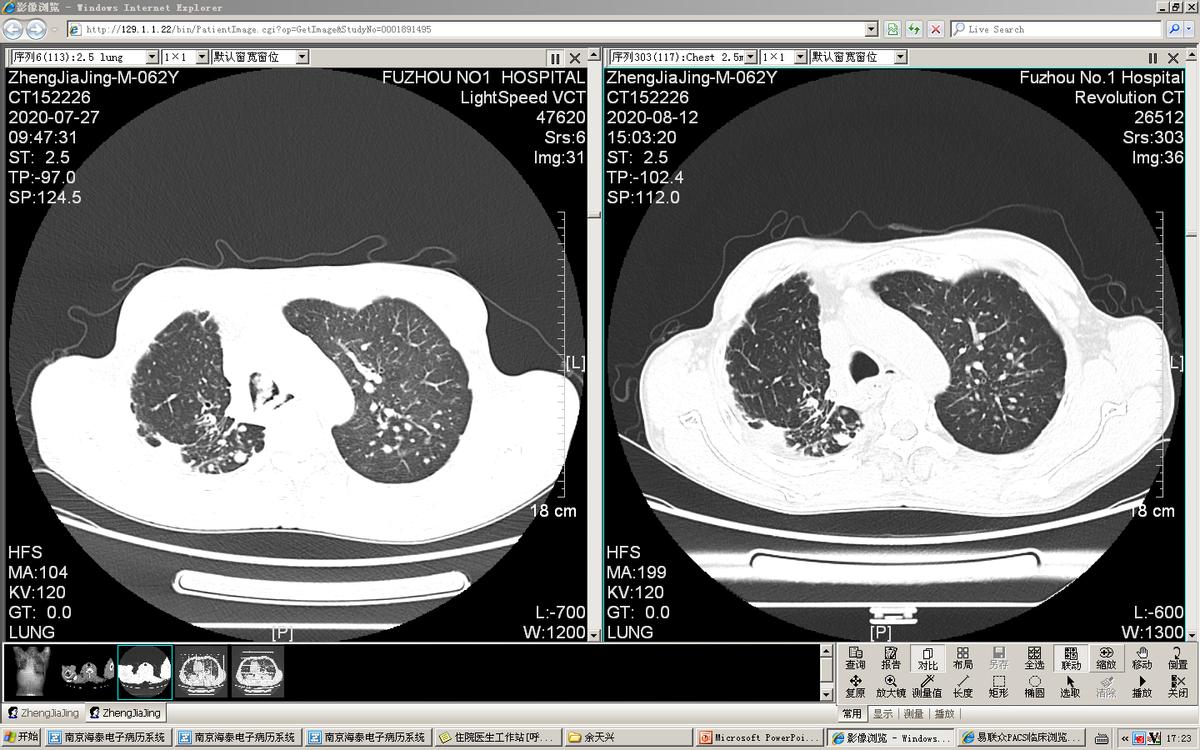

最严重的一次是1年前李先生喘得都动不了,家里人叫了救护车送过来治疗。查肺CT可见肺部里面及气道里面多处肿瘤复发、转移。

这次因为李先生状态不好,而且气管内肿瘤多,气道堵塞严重,手术风险高,我们团队讨论后,觉得用硬质气管镜联合电子支气管下对李先生气道内肿瘤进行切除比较安全。很庆幸,虽然手术比较难,但是手术很顺利,我们把气管内的肿物都清除干净了。切完后李先生气喘也明显好转了,最后他是自己走着出院的。